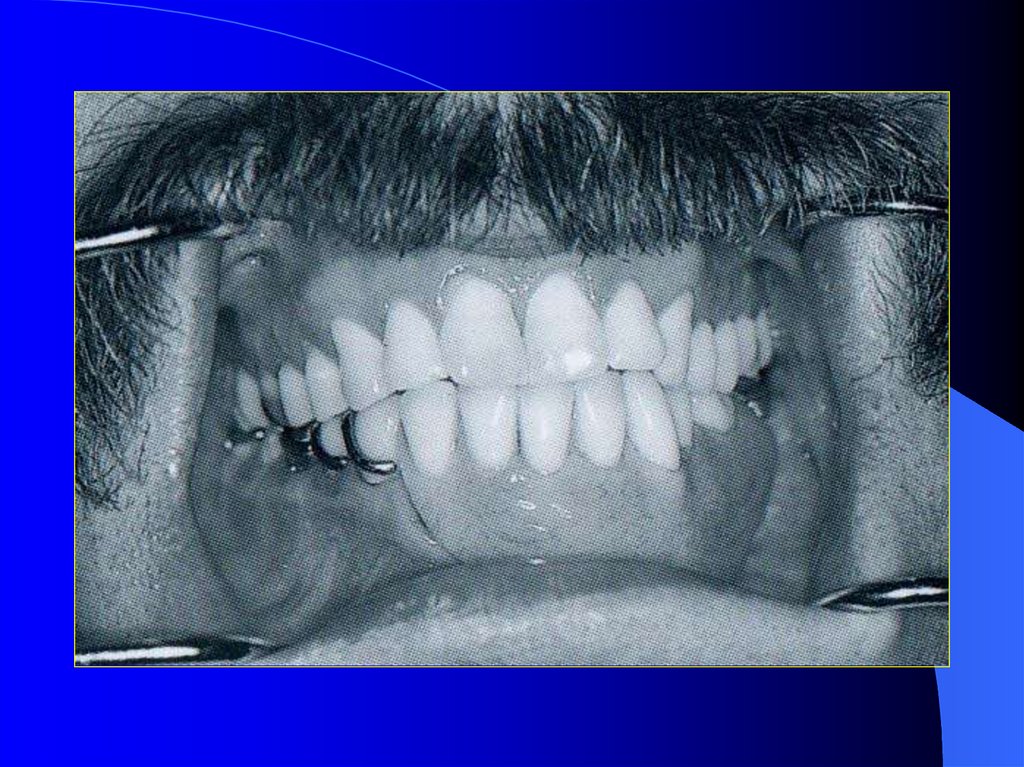

14. Mandibuler devamlılığı olmayan dişli hastalar

Altçene devamlılığının

bozulduğu durumlarda

çeneler arası ilişkiler ve

oklüzyon değişir.

Altçene defektli tarafa

doğru yan ve ileri

hareketleri yapamaz yada

çok kısıtlı olarak

yapabilir.